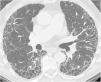

La patología de las vías respiratorias de medio calibre (bronquios segmentarios y subsegmentarios) es común y se presenta con síntomas respiratorios poco específicos, como tos, infecciones de repetición y en ocasiones hemoptisis. La dilatación permanente del árbol bronquial se conoce como «bronquiectasia» y representa un reto diagnóstico. El análisis de la distribución regional de las bronquiectasias en los diferentes lóbulos pulmonares es la guía diagnóstica más útil. El objetivo de este trabajo es describir los hallazgos de imagen de las bronquiectasias y sus diferentes tipos, revisar las situaciones más comunes y proponer un algoritmo diagnóstico basado en su distribución anatómica. Las bronquiectasias son un hallazgo frecuente, resultado de un amplio espectro de enfermedades. Los estudios de imagen desempeñan un papel esencial en su detección, clasificación y orientación diagnóstica hacia la patología subyacente

Diseases that involve the medium caliber airways (segmental and subsegmental bronchi) are common and present clinically with nonspecific respiratory symptoms such as cough, recurrent respiratory infections and occasionally, hemoptysis. The abnormal and irreversible dilation of bronchi is known as “bronchiectasis”. The diagnosis can be challenging and the analysis of the regional distribution of the bronchiectasis is the most useful diagnostic guide. The objective of this manuscript is to describe the main imaging findings of bronchiectasis and their classification, review the diseases that most commonly present with this abnormality, and provide an approach to the diagnosis based on their imaging appearance and anatomic distribution. Bronchiectasis is a frequent finding that may result from a broad range of disorders. Imaging plays a paramount role in diagnosis, both in the detection and classification, and in the diagnosis of the underlying pathology.